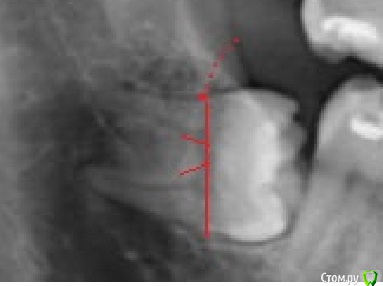

kamranchick Опубликовано 5 апреля, 2015 Поделиться Опубликовано 5 апреля, 2015 добрый день.Можно ли ортодонтически вытащить 8ой зуб на место 7, а 7ой на место 6гоИ будет ли потеря чувствительности после ретракции? судя по снимку травма будет значительная Ссылка на комментарий

Bier Опубликовано 6 апреля, 2015 Поделиться Опубликовано 6 апреля, 2015 почему? я думаю если задаст.целью то можно. А что не стоит это точно.подъедет полунаклоненный зуб с резорбированными корнями, через 3 года )) 6 Ссылка на комментарий

kamranchick Опубликовано 7 апреля, 2015 Автор Поделиться Опубликовано 7 апреля, 2015 Сам работаю в поликлиннике, кроме долот элеваторов и щипцов ничего нет.Думаю попробую взять портативную машинку и вот такой план будетРезекция костного участка, распил коронки, потом с помощью долота разделить корни, помоему их там 3 и вытащить с помощью элеваторов.Какие будут комментарии? Ссылка на комментарий

kladoffka Опубликовано 7 апреля, 2015 Поделиться Опубликовано 7 апреля, 2015 А долотом можете компрессию нерва сделать и если парестезия останется на всю жизнь, то эмфизема пройдет за неделю. Плюс ударами неплохо по внчс отдаёт 4 Ссылка на комментарий